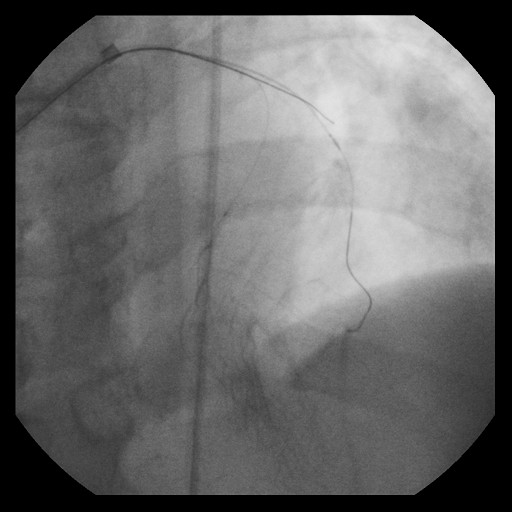

Re-attempted PCI for LAD CTO was planned. The procedure was performed with an 8-Fr, SPB 3.5 SH for the antegrade approach and a 6-Fr IMA for retrograde angiography. Primary antegrade approach was performed because there were no feasible collateral channels. Gaia Next 3 could penetrate the proximal cap of CTO. Since Gaia Next3 could not proceed into the CTO mid portion, the guide wire was escalated to Gaia Next 4. However, Gaia Next 4 advanced into extra plaque space beyond the CTO distal true lumen angiographically. Therefore, we decided to perform tip-detection (TD) method using intravascular ultrasound (IVUS). IVUS revealed that the guide wire proceeded into extra plaque from the CTO proximal portion, although the CTO entry was in the intra plaque space. At first, we tried TD-intra plaque tracking (IPT) in the CTO body. However, Conquest Pro 12 ST (CP-12ST) could not penetrate the CTO body. Therefore, we performed TD-antegrade dissection andreentry (ADR). Eventually, CP12 ST succeeded to puncture the distal true lumen supported by a Caravel. We implanted a drug-eluting stent, which resulted in successful revascularization.